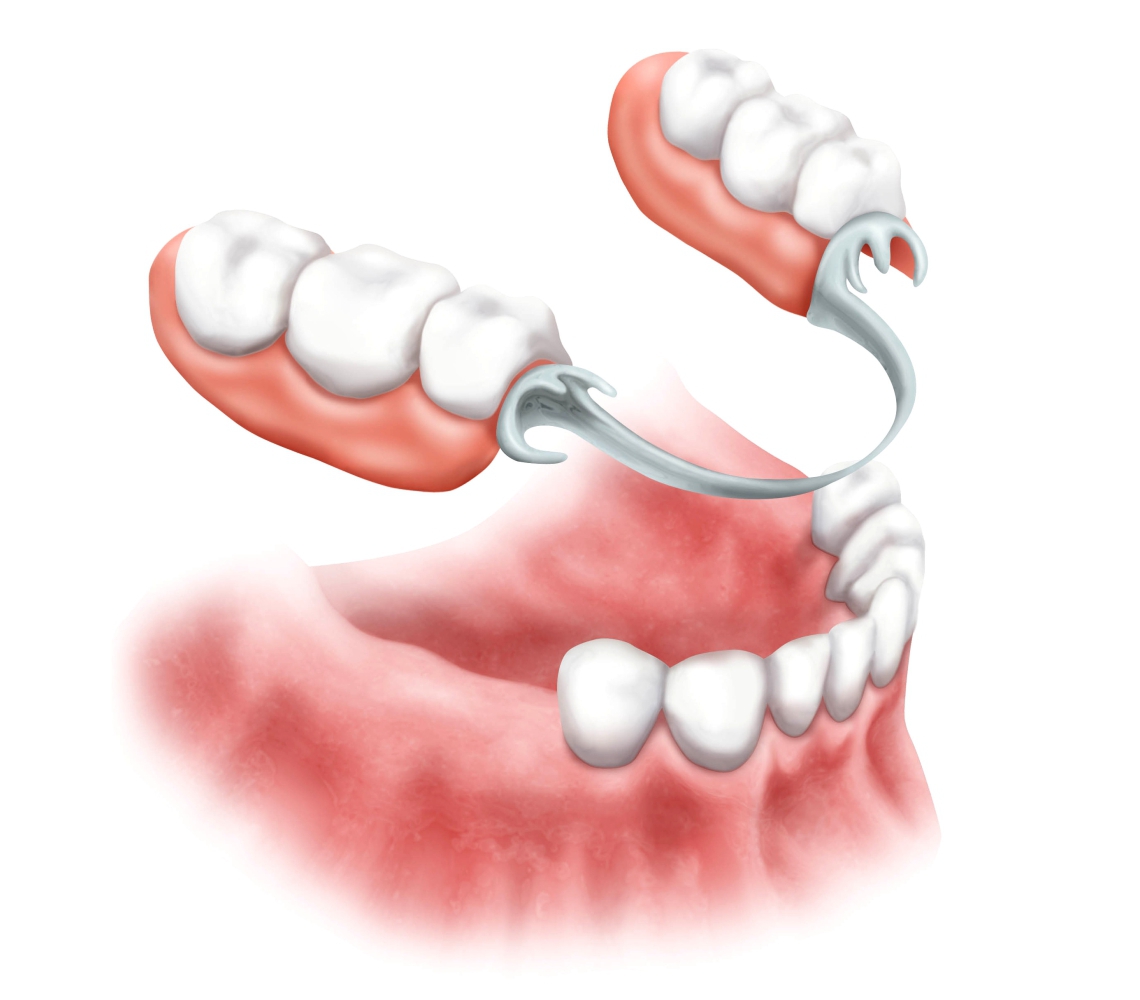

Современные методы протезирования зубов: Рекомендации и советы